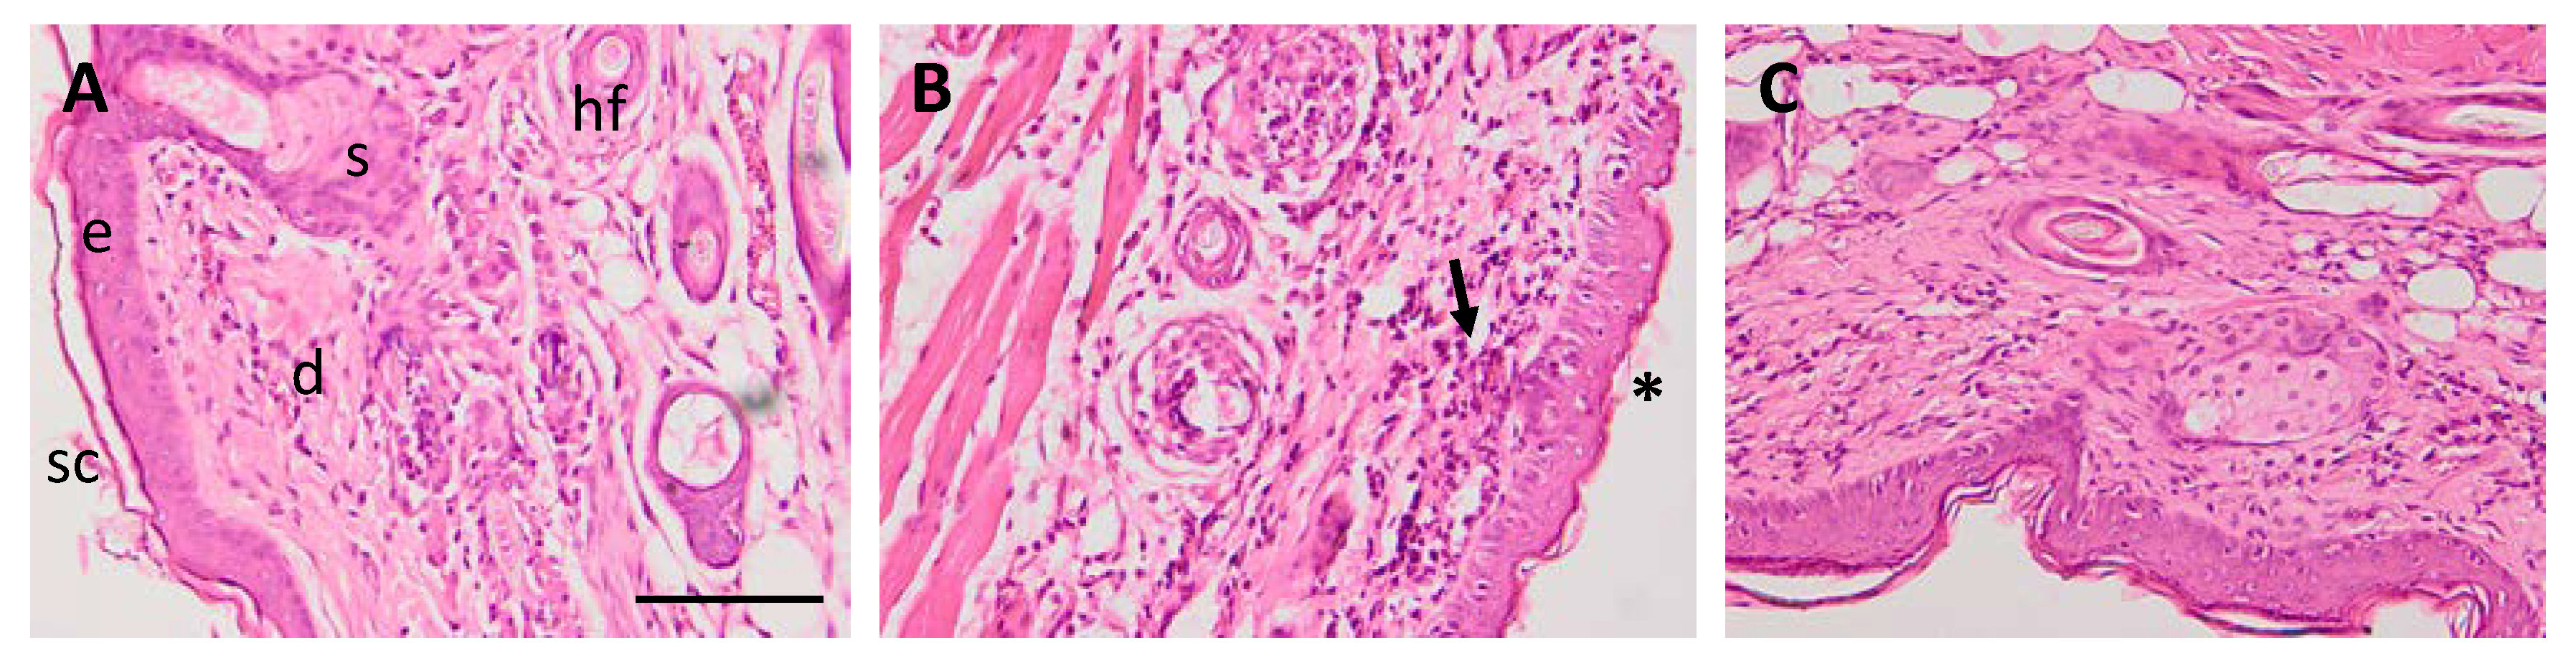

3.5.3. Histological Analysis